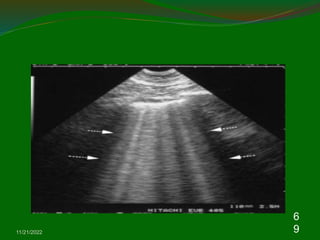

11/21/2022

6

9

Consolidation

 Irregular hypoechic area of varying size and

shape.

 Echotexure can appear homogenous or

inhomogenous.

 The most common sonographic feature is the

air bronchogram which is characterized by lens

shaped internal echoes within hypodene area

or echogenic lines.